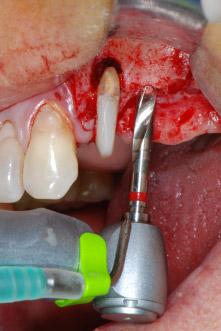

Implant beds were prepared at sites 25 and 26 with rotary instruments, used in a contra-angle handpiece with a 20 : 1 transmission ratio with an updated powerful implant motor (Implantmed, W&H) (Fig. 8).